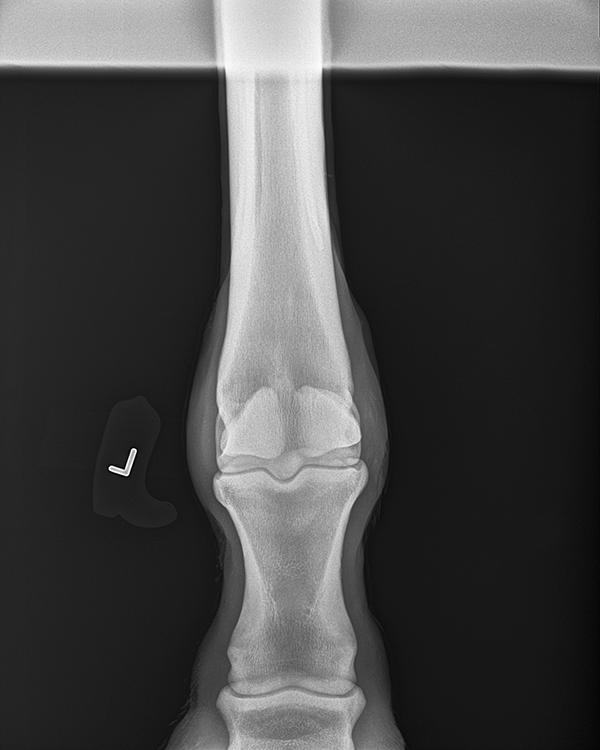

craniocaudal projection of the elbow